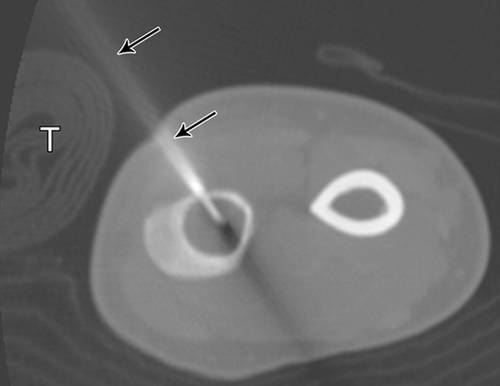

12 - 52岁女性内生软骨瘤。

轴位图显示胫骨活检(绿色和箭头)的最佳入口位置,避免肌肉室。T =胫骨,F =腓骨。

11 -小腿的插图。